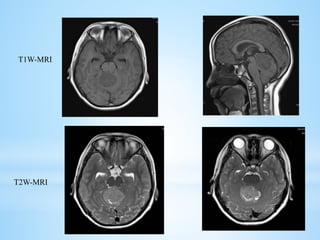

 MRI: There is a high degree of variability of MR appearances of medulloblastoma.

 T1 sequences are usually iso-hypointense to white matter and hyperintense on T2

sequences.

T1W-MRI

T2W-MRI